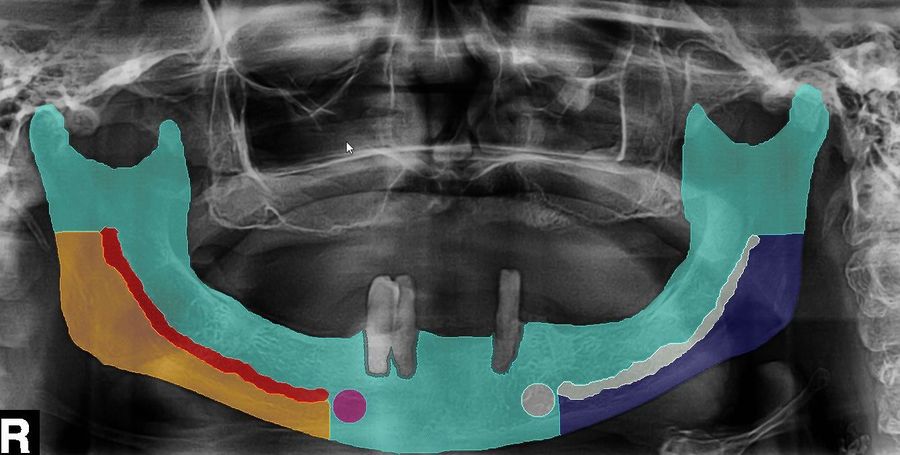

More than 200 patient records and image data (panoramic radiographs, computed tomography and cone beam computed tomography scans) were collected from a retrospective series of patients affected by ARONJ, by oral cancer with jaw bone involvement (reference group 1), as well as patients requiring dental implants (reference group 2). Labeling of the panoramic radiographs, computed tomography as well as cone beam computed tomography was performed. An AI workflow was developed that allowed for the data to be analysed within less than one minute.